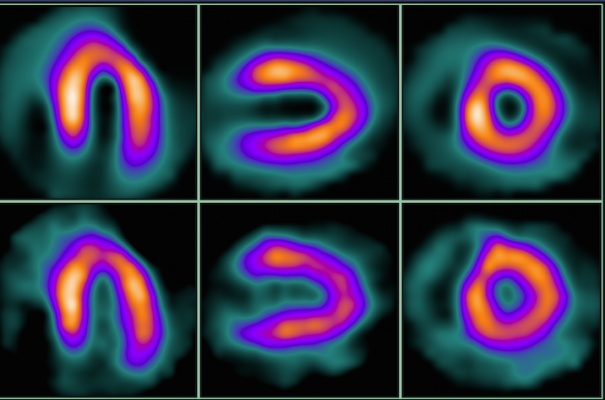

Myocardial Perfusion SPECT: Background, Indications, Contraindications Interpretation of SPECT/ CT Myocardial Perfusion Images: Common Arti- facts and Quality Control Techniques1 Heart attack, SPECT scan - Stock Image - C013/1043 - Science Photo Library Spect Scan Heart